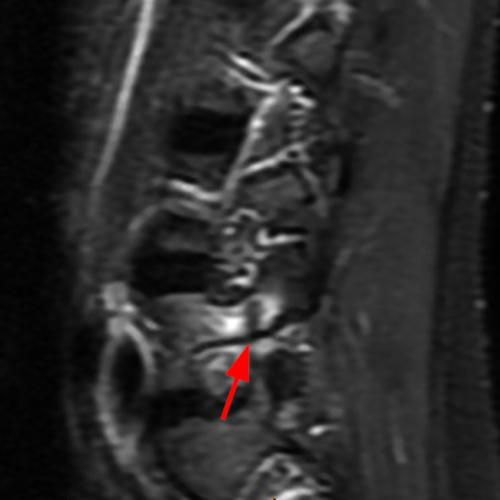

Case 1: T2-weighted axial (3A) and sagittal STIR (3B) sequences show marked cortical T2/STIR hyperintensity in the left pedicle of L5 surrounding a hypointense line (arrows) which begins at the inferior/medial margin of the pedicle and nearly completely traverses the pedicle.

Case 1: Acute left-sided pediculolysis